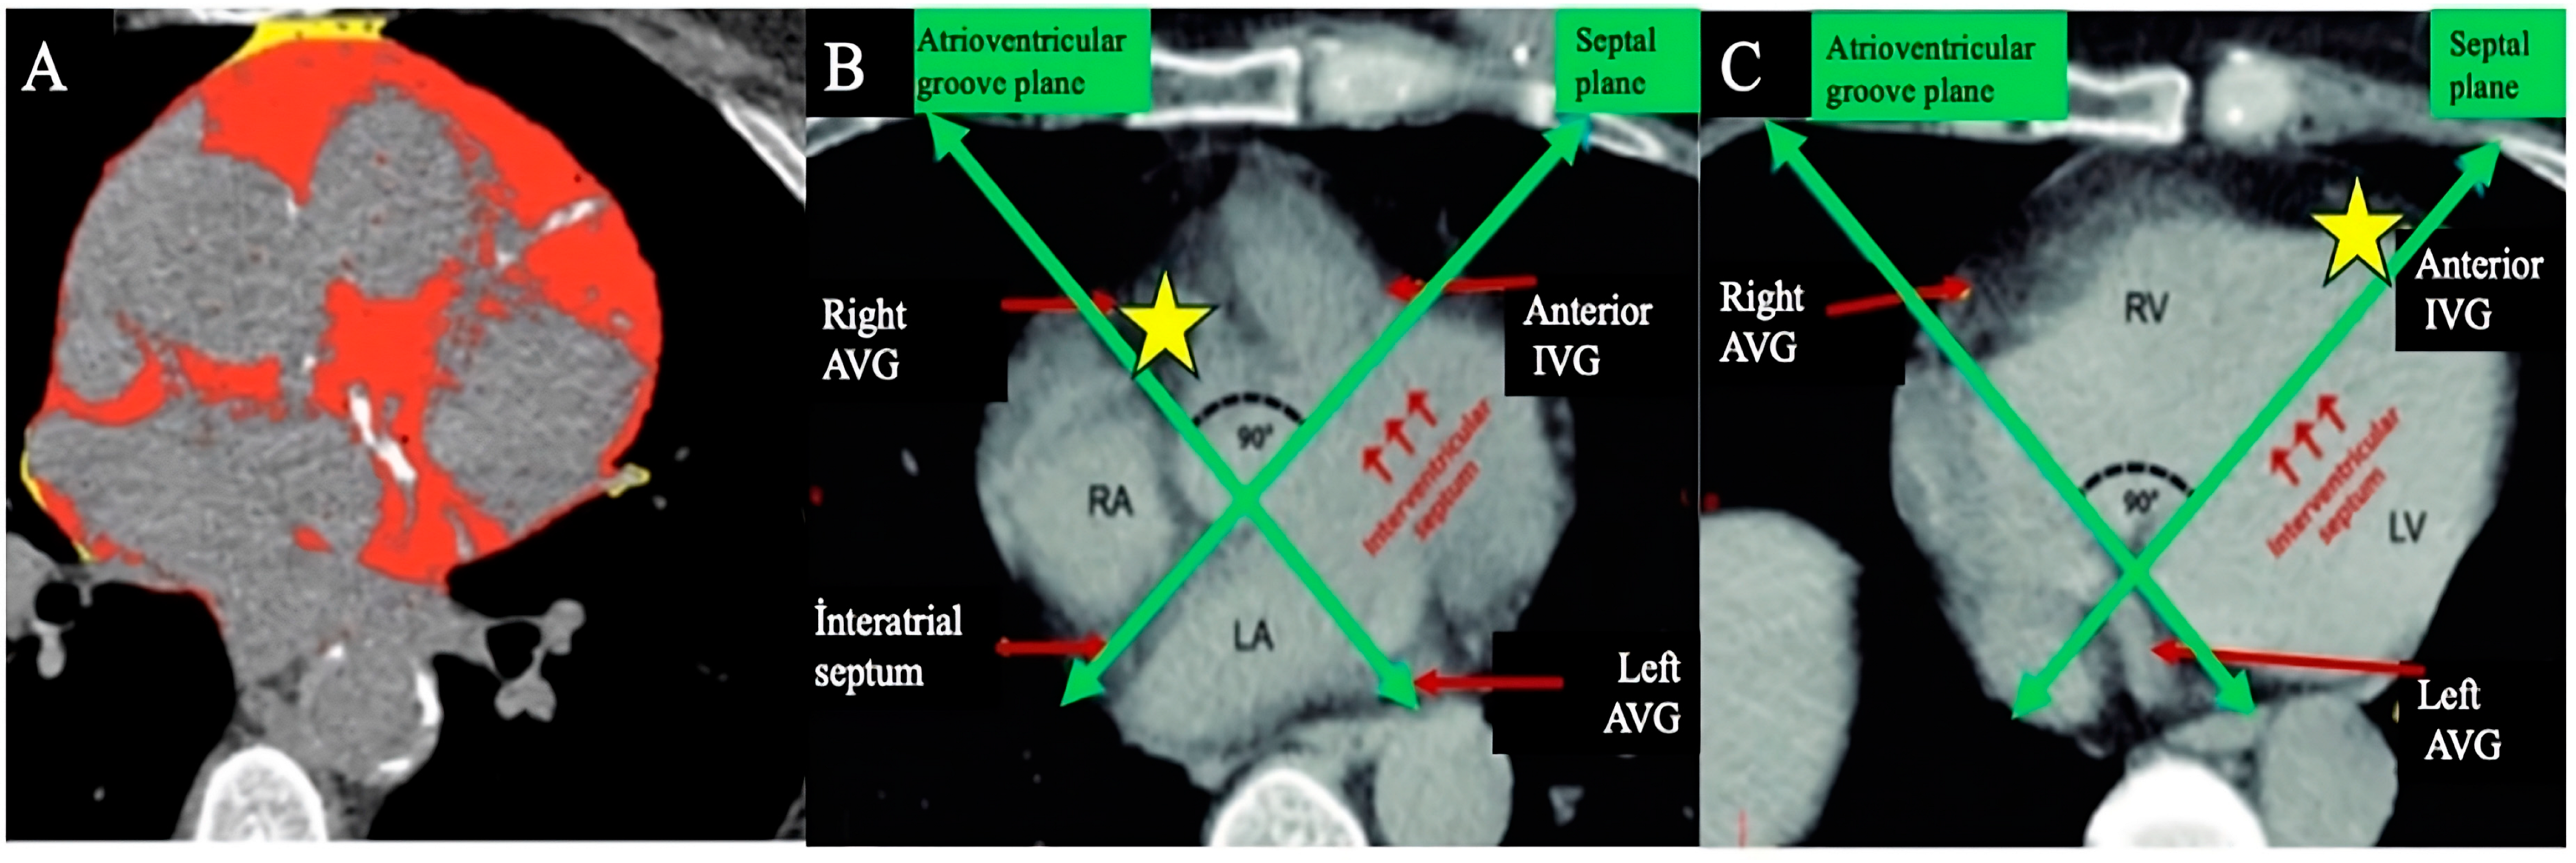

| Thorax CT-CACS | 3.5 (1–6.7) | 0 (0–3) | <0.001 |

| Thorax CT-CACS +, n (%) | 84 (%81) | 100 (%45) | <0.001 |

| Thorax CT—aortic calcification +, n (%) | 86 (%82.7) | 103 (%46.6) | <0.001 |

| Thorax CT-EAT (HU) | −82.7 ± 15.9 | −90.2 ± 16.5 | <0.001 |

| Thorax CT CAC + aortic calcification + | 5.28 | 3.13–8.91 | <0.001 | 3.85 | 1.69–8.78 | 0.001 |

| C | CACS + Aort calcification + | 1 point |